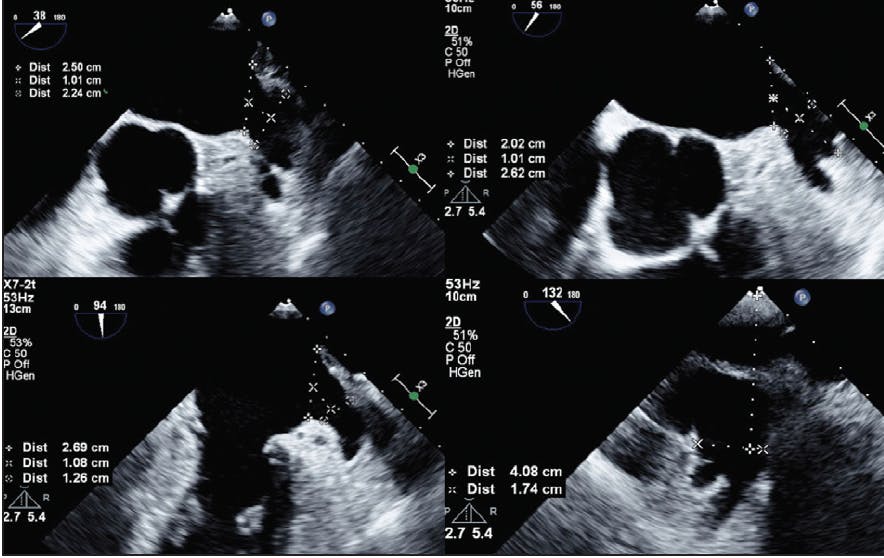

Transesophageal echocardiography (TEE) remains the most commonly used imaging modality to plan for and guide LAAO worldwide (Figure 1). However, there is a growing interest in cardiac CTA (CCTA) for preprocedural planning and postprocedural surveillance (Figure 2).2,3 Regardless of the chosen imaging modality, the essential data needed by the interventionalist to achieve safe and efficient LAAO include determinants of LAA suitability for closure and predictors of a challenging LAA procedure (Table 1).

Figure 1. Sizing of the LAA for implanting an Amulet device (Abbott) using two-dimensional TEE.

LAA sizing.  The diameter and depth of the LAA are the two most important elements needed for anatomic suitability screening. Unfortunately, there is considerable variability in measuring and reporting those dimensions in clinical practice. For example, an LAA with an acute chicken wing anatomy may be reported to have a 32-mm depth, but only 16 to 18 mm of this depth can be used to perform the LAAO procedure. Similarly, the ostial diameter is commonly measured at a different location than the intended landing zone for the specific device. Although several landmarks can be used to report those dimensions (eg, left circumflex coronary artery), the best ostial and depth measurements for the procedure are those that are performed by an interventional imager who is (1) familiar with the LAAO devices used in their interventional lab and (2) able to envision/simulate device deployment while performing the screening imaging. Essentially, the operator needs to know if the LAA is amenable for closure with a certain LAA occluder. Published sizing criteria can be a useful guide to determine suitability for LAA closure4; however, they cannot replace the foresight of an experienced interventional imager who can simulate the implant either conceptually or with the use of advanced imaging techniques (three-dimensional [3D] TEE reconstruction, 3D printing, or CCTA simulator software).